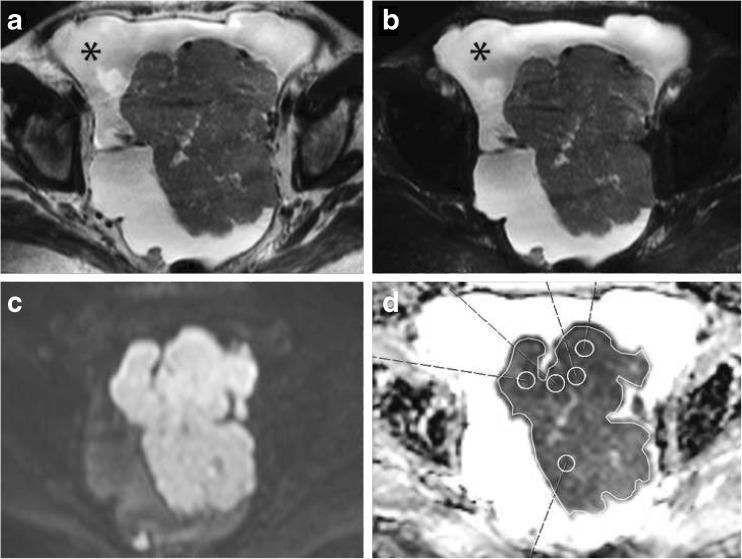

DWI was performed prior to surgery. Two observers used whole lesion single plane region of interest (WLsp-ROI) and five small ROIs (S-ROI) to analyze ADCs. Samples from tumours and metastases were collected during surgery. Immunohistochemistry and quantitative reverse transcription polymerase chain reaction (qRT-PCR) were used to measure the expression of vascular endothelial growth factor (VEGF) and its receptors.

The interobserver reliability of ADC measurements was excellent for primary tumours ICC 0.912 (WLsp-ROI). Low ADCs significantly associated with poorly differentiated OC (WLsp-ROI P = 0.035). In primary tumours, lower ADCs significantly associated with high Ki-67 (P = 0.001) and low VEGF (P = 0.001) expression. In metastases, lower ADCs (WLsp-ROI) significantly correlated with low VEGF receptors mRNA levels. ADCs had predictive value; 3-year overall survival was poorer in patients with lower ADCs (WLsp-ROI P = 0.023, S-ROI P = 0.038).

Reduced ADCs are associated with histological severity and worse outcome in OC. ADCs measured with WLsp-ROI may serve as a prognostic biomarker of OC.

• Reduced ADCs correlate with prognostic markers: poor differentiation and high Ki-67 expression • ADCs also significantly correlated with VEGF protein expression in primary tumours • Lower ADC values are associated with poorer survival in ovarian cancer • Whole lesion single plane-ROI ADCs may be used as a prognostic biomarker in OC.